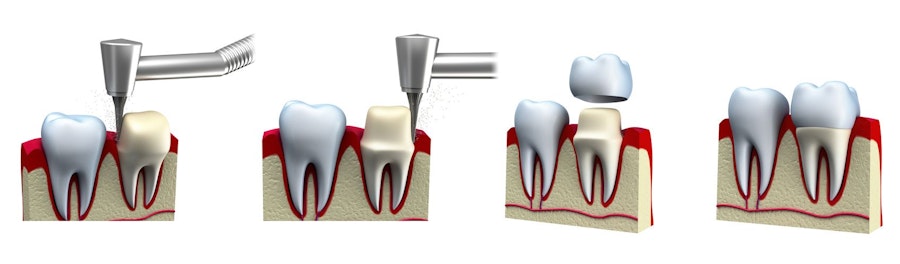

La mise en place des couronnes dentaires

Le processus de traitement de la couronne en porcelaine nécessite une ou deux visites à notre bureau, en fonction de vos besoins particuliers. Les étapes générales de la procédure comprennent:

- Préparation de la dent: Le Docteur Casey remodèlera la dent pour créer une base appropriée pour la couronne. Toute partie pourri ou endommagée sera retirée au cours de cette étape.

- Impressions: Une fois la dent traitée, nous prendrons des empreintes qui guideront les techniciens de notre laboratoire partenaire. Nous fournirons également au laboratoire des instructions spécifiques pour faire correspondre la couleur de votre couronne à vos dents. (Les patients admissibles aux couronnes conçue en même journée recevront leur restauration au cours du même rendez-vous

- Couronne provisoire: Si votre couronne est fabriquée par le laboratoire dentaire, le Docteur Casey fera adhérer votre couronne temporaire en place afin protéger la dent jusqu'à ce que votre restauration finale soit terminée.

- Fabrication de la couronne finale: En général, il faut environ deux à trois semaines à un technicien de laboratoire pour fabriquer votre couronne personnalisée. (Les couronnes conçues de journée même seront fabriqués sur place en utilisant notre machine de fraisage en bureau pour les patients admissibles.)

- Emplacement de la restauration finale: Une fois que votre couronne de porcelaine est créée, le Docteur Casey évaluera la forme et fixera votre nouvelle restauration en place. Le résultat sera un sourire attrayant et entièrement fonctionnel.